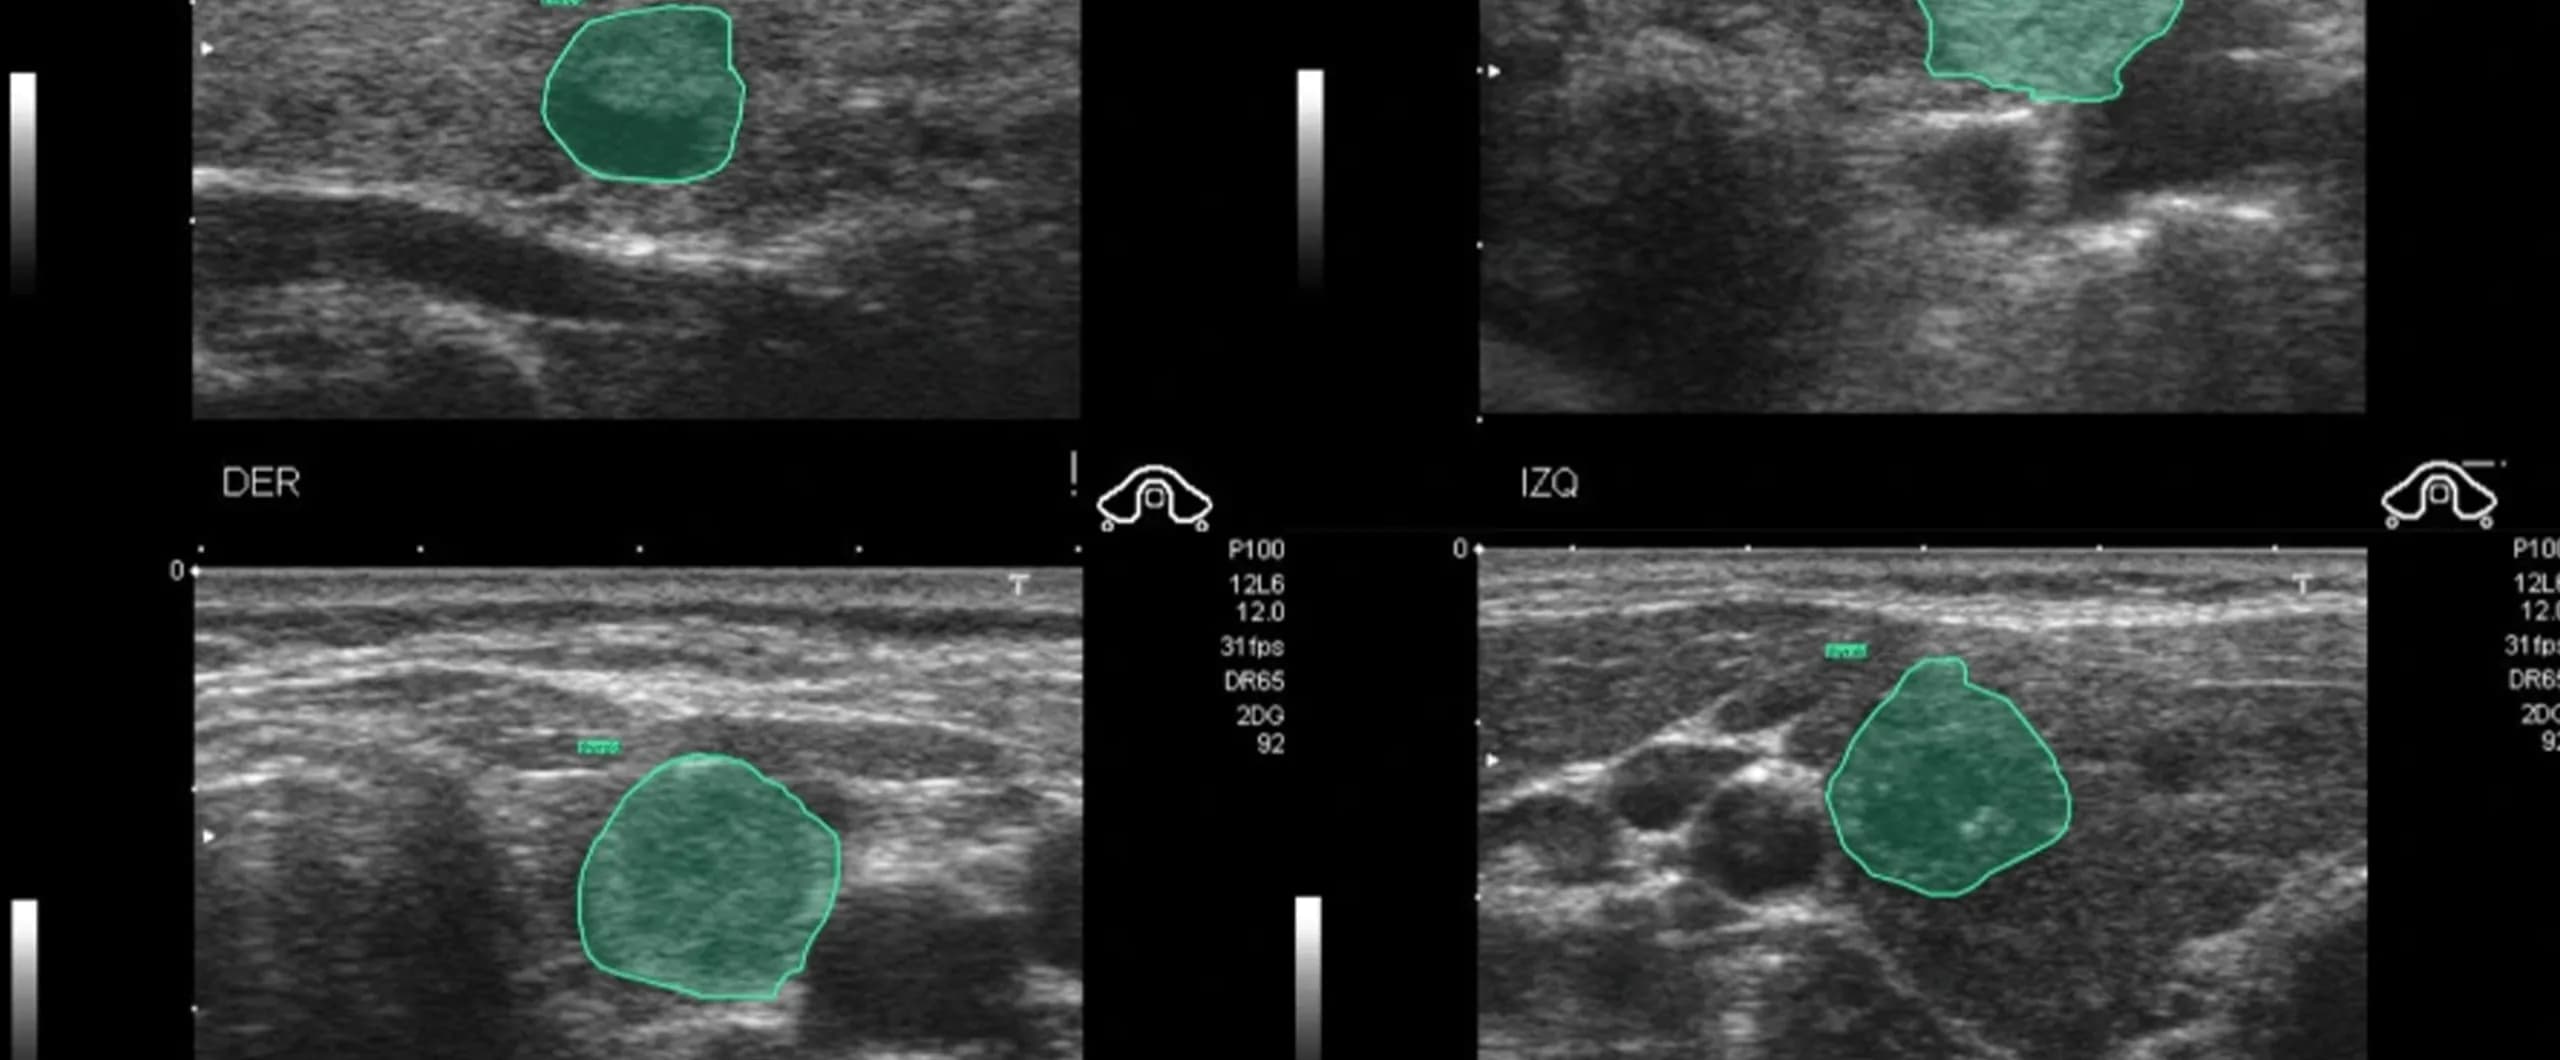

The mission: Advance thyroid diagnostics to facilitate decision-making

The client’s vision was to reshape how thyroid conditions are diagnosed and understood by leveraging the precision and scalability of artificial intelligence. Their goal was to lay the foundation for AI-powered tools that could support clinicians in delivering faster, more accurate, and accessible thyroid diagnostics across the region. To achieve this, they needed more than just data. They needed authentic clinical knowledge embedded into their model through expertly annotated imaging data. This required collaboration with 50 qualified medical professionals across Southeast Asia (Philippines, Indonesia, Vietnam, Malaysia, and Singapore) who could bring domain expertise to every annotation, ensuring the model was grounded in real-world diagnostic accuracy.